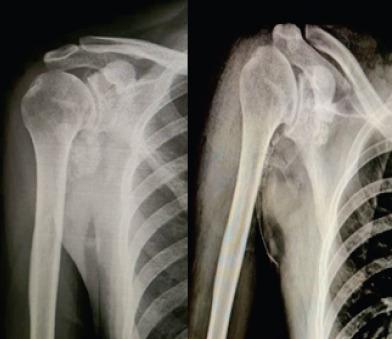

Here, we report a rare case of synovial chondromatosis affecting the right shoulder joint in a 23-year-old male with a 5-year disease duration who presented with progressive pain and restriction in movements which were impacting his routine activities. The loose bodies were removed using the arthroscopic approach combined with a partial synovectomy, and intra-articular methylprednisolone post procedure. The patient showed an excellent recovery in joint mobility within 4 weeks post-operatively, and there were no clinical signs of recurrence during a 6-month follow-up period.

在此,我们报告一例罕见的滑膜软骨瘤病病例,该病例发生在一名23岁男性的右肩关节,病程为5年,患者出现进行性疼痛和活动受限,影响其日常活动。采用关节镜手术联合部分滑膜切除术取出游离体,并在术后关节腔内注射甲基强的松龙。患者术后4周内关节活动度恢复良好,在6个月的随访期内无复发的临床迹象。